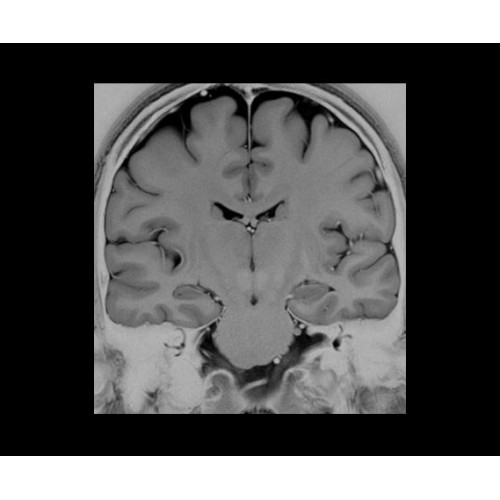

SIGNA PET/MR 3.0T — это гибридная система, в которой совмещаются две принципиально разные технологии — магнитно-резонансную томографию (МРТ) и позитронно-эмиссионную томографию (ПЭТ). Система отличающийся высокой чувствительностью и эффективностью и предназначена для диагностики в области онкологии, неврологии, кардио-васкулярных исследований, исследований воспалительных процессов.

Компания GE Healthcare представляет революционную, полностью интегрированную систему SIGNA PET/MR1, в которой сочетаются времяпролетная технология (TOF) и возможности напряженности магнитного поля 3.0 Тл. Мы поможем вам поднять исследования на более высокий уровень. SIGNA PET/MR позволяет достичь впечатляющей точности и скорости исследований, а благодаря новейшей технологии реконструкции Q.Clear2 качество изображений улучшается в два раза. Кроме того, в систему включен полный набор клинических приложений и гибких катушек для проведения любых видов исследования, открывая для вас возможности визуализации, о которых вы даже не догадывались.

Впечатляющие клинические возможности

Система SIGNA PET/MR предлагает впечатляющие клинические возможности и открывает доступ к наиболее полным пакетам программных приложений.